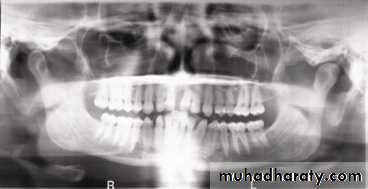

In a good panoramic radiograph:

The mandible is “U” shaped.The condyles are positioned about equal distance from the inside edges of the image and 1⁄3 of the way down from the top edge of the image.

The occlusal plane exhibits a slight curve or “smile line,” upwards.

The roots of the maxillary and mandibular anterior teeth are readily visible with minimal distortion.

Magnification is equal on both sides of the midline.